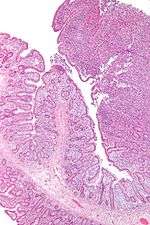

| Micrograph of enteropathy-associated T cell lymphoma (upper right of image). H&E stain. | |

Enteropathy-associated T-cell lymphoma (EATL), also enteropathy-type T-cell lymphoma (ETTL), is a type of T-cell lymphoma that affects the small intestine. It is the most common primary gastrointestinal T-cell lymphoma, arising from the T cells that are found between the cells that line the small intestinal (brush border cells or small intestinal epithelial cells).[1] These cancerous T-cells are a possible consequence of refractory cases of coeliac disease or in chronic, untreated cases in genetically susceptible individuals.